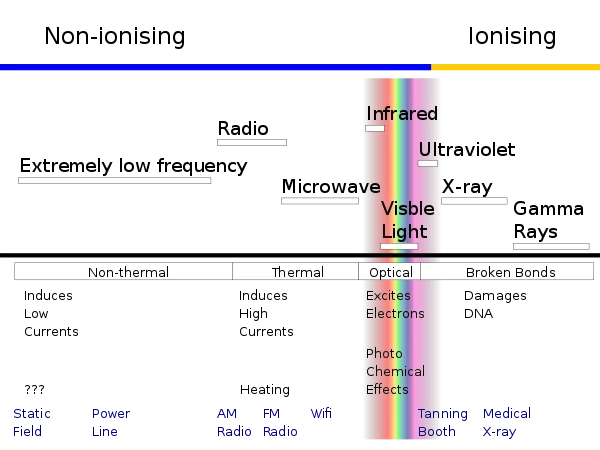

辐射大致分两类,电离辐射和非电离辐射,区别在于波的长短

按照能量的多少,辐射大体上能分两类,电离辐射和非电离辐射,后者也有叫电磁辐射的。这两者相比,电离辐射携带的能量更多、波长更短、频率更高,能够在分子和原子级别上实现「打击」,让电子离开原有的运行轨道,也就是「电」、「离」了。非电离辐射就远没有这么大能耐。

电离辐射那就不太常见了,比如伽马射线、X 射线、被大气层拦在地球之外的远紫外线都算。而我们常识中的各种辐射源,什么微波炉啊、手机啊、电脑啊,通通是非电离辐射,不危险。除了部分工作特殊,需要长时间接触电离辐射的人之外,咱们普通人还真没必要防辐射如防贼。